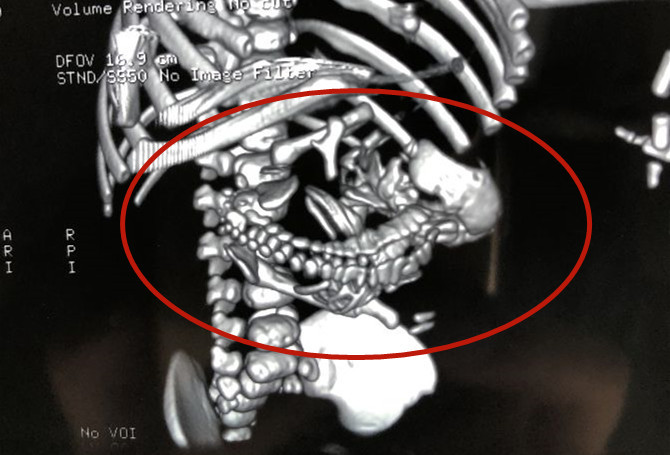

經過周密的術前檢查,醫生4天後給男嬰做了開腹手術。術中發現,寄生胎的基底部有很多來自於腹主動脈和胰腺動脈的大血管,像蜘蛛網一樣,任何一點損傷就會造成大出血。

楊星海說,「寄生胎」是一種罕見的先天性疾病,遺傳學上又稱胎內胎,發病率約為五十萬分之一,是指完整胎體的某部分寄生有另一個或幾個不完整的胎體,「寄生胎無獨立生存能力,但在寄主體內仍是活的組織,並隨寄主的成長而增大。」他驚歎,寄生胎手術自己總計完成6例,「但像這例頭顱、四肢、脊柱如此完整的還是第一次碰到。」